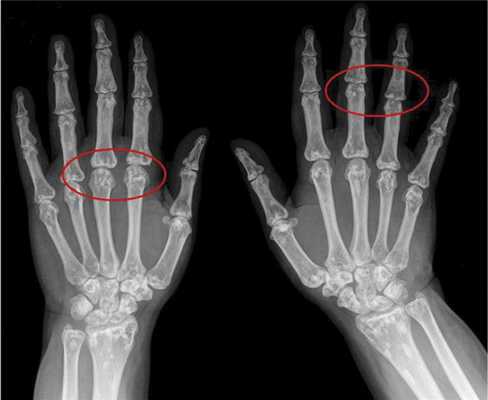

Вторым по частоте встречаемости признаком является поражение костной системы в виде остеопойкилии (синонимы — врожденная рассеянная склерозирующая остеопатия, врожденная пятнистая множественная остеопатия), возникающей в результате очагового отложения кальция [3, 5]. Признаки остеопойкилии обнаруживаются преимущественно в костях конечностей и плечевого пояса. Клинически они не вызывают жалоб, но важны для дифференциальной диагностики. При рентгенологическом исследовании в костях выявляются мелкие округлые или овальные уплотнения спонгиозных структур костной ткани (рис. 2).

Рис. 2. Остеопойкилия.

Для определения изменений в скелете делают рентгеновские снимки кистей и стоп. Поскольку поражения костей в детстве в основном не замечаются, эти характеристики синдрома Бушке-Оллендорфа обнаруживаются только в пожилом возрасте. Типичные изменения костей не наблюдаются до 15 лет.

На рентгенограмме видны увеличенные и слегка утолщенные трабекулы, то есть небольшие трабекулы на кости. Эти аномалии кости не следует путать с метастазами в кости или мелореостозом (утолщением кости). Если возникает боль, синдром Бушке-Оллендорфа возникает не сразу.

Рентгенологически на фоне почти нормальной кости в губчатом веществе эпифизов и метафизов длинных трубчатых костей, плюсневых и пястных костей, фаланг наблюдаются пятнистые очаги затемнения. Реже поражаются позвонки, рёбра, грудина, череп. Иногда заболевание сочетается с синдромом синих склер, несовершенным костеобразованием, дебильностью, эпилепсией.